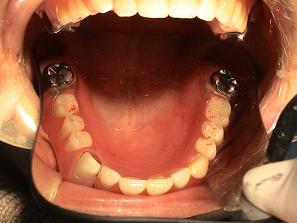

3.

バネなし入れ歯を入れた

状態です!!

* 金属のバネがないので

見栄えが良いです!

入れ歯が入っているとは

気がつかれにくいです!!